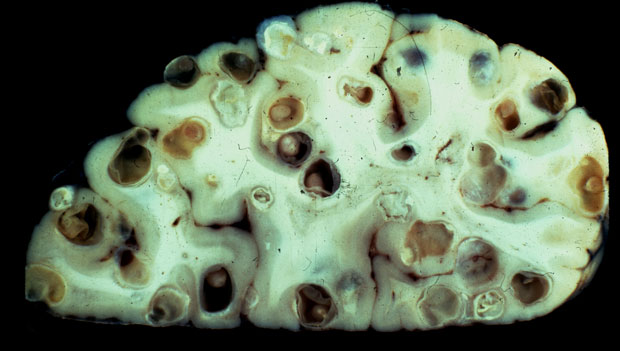

Before they become adults, tapeworms spend time as larvae in large cysts. And those cysts can end up in people’s brains, causing a disease known as neurocysticercosis. … As a tapeworm cyst grows, it may push against a region of the brain and disrupt its function. It may get stuck in a passageway, damming the flow of cerebrospinal fluid. This impasse can cause hydrocephalus, or water on the brain, along with dangerously high pressure. A resulting brain hernia can result in stupor, coma, or death.

(Image by Theodore Nash)